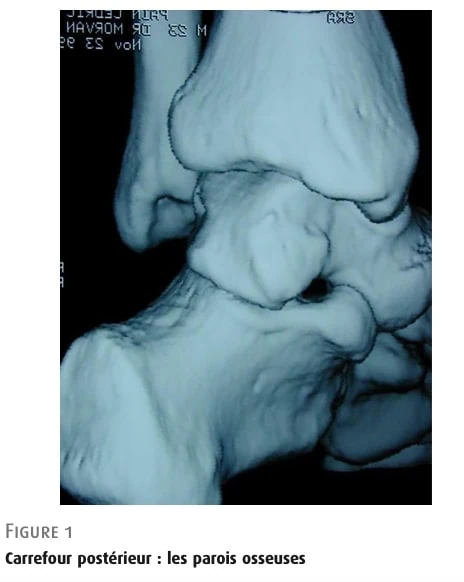

后踝关节室上以胫骨骨骺远端边缘为界,下以跗骨小关节后方为界。

图 1

后踝关节室:骨学。

距骨后侧

在胫骨后缘和小腿骨之间是距骨后侧,其突出程度有大有小(图 2)。 它有两个后结节:一个较小的后内侧结节和一个较大的后侧面结节。 后者来自于 8 至 13 岁时出现的继发性骨化中心的融合。 其大小不一,可以增大,有时超过 1 厘米(Stieda 凸起)。 两个小结节之间是结节间沟,屈肌腱(FHL)在此运行。

图 2: 距骨后方 距骨后侧: 1 后外侧结节 2: 结节间沟